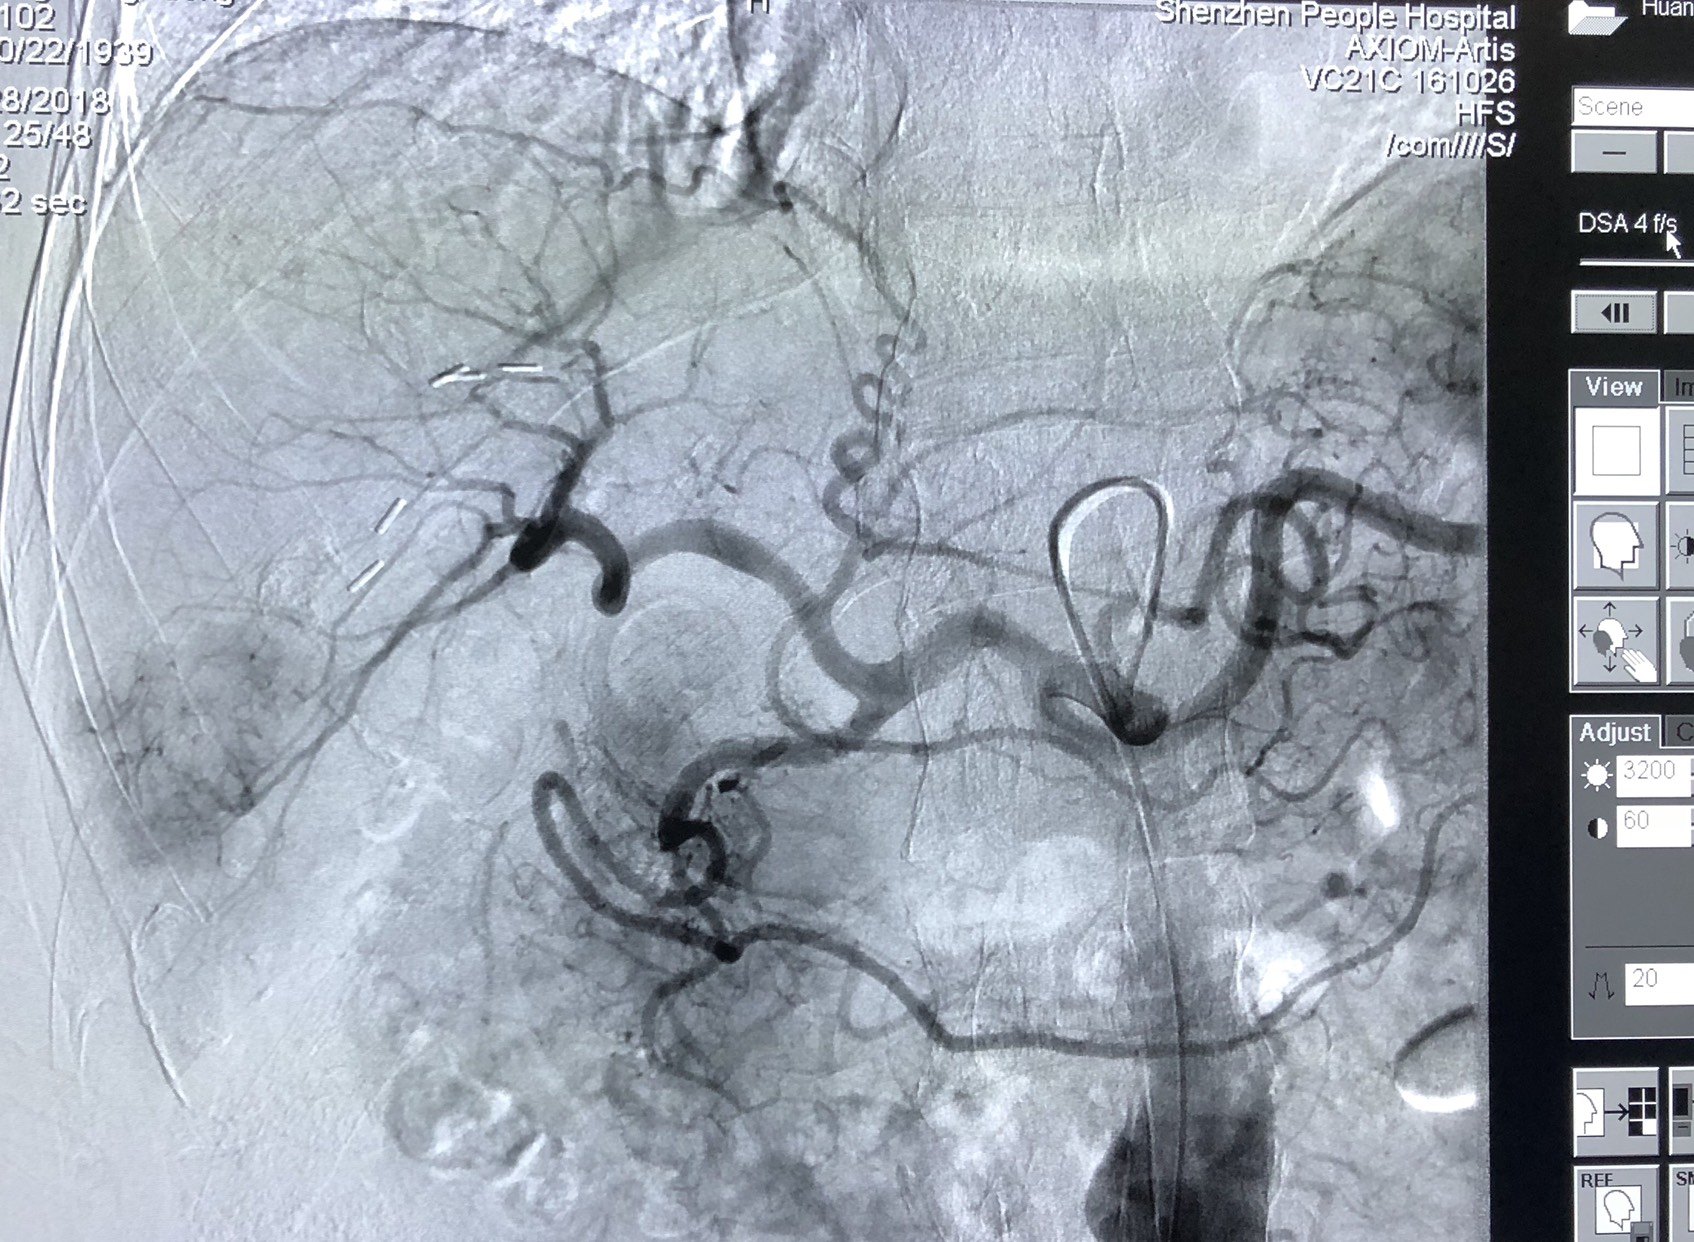

肝动脉造影,明确肿瘤染色